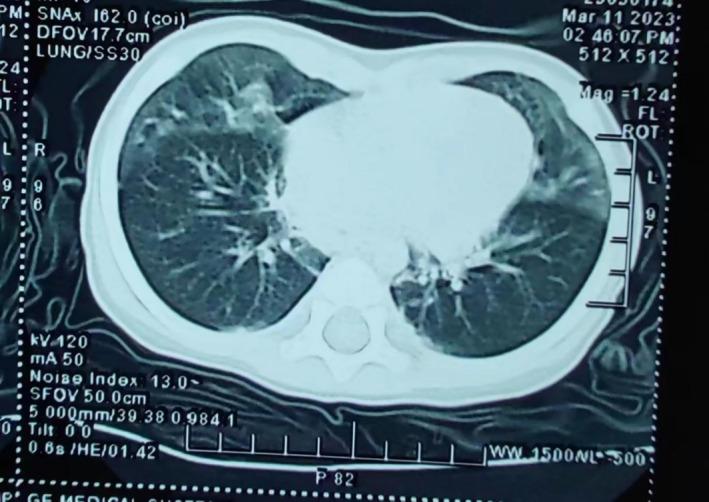

It Is Time to Get to Know the Neuroendocrine Cell Hyperplasia of Infancy.

In the two decades that have elapsed since the initial proposal of neuroendocrine cell hyperplasia of infancy (NEHI), several hundred cases have been reported and researched. However, a comprehensive analysis of research progress remains absent from the literature. The present article endeavors to evaluate the current progress of NEHI research and offer a reference for the clinical management of this condition.